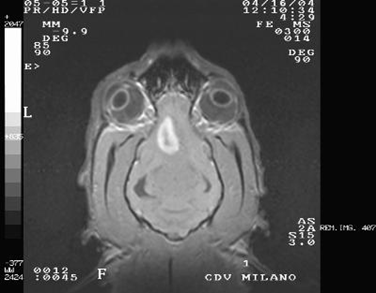

- Risonanza magnetica: è l’esame di diagnostica per immagini più affidabile per il riconoscimento di patologie prosencefaliche che causano crisi convulsive.